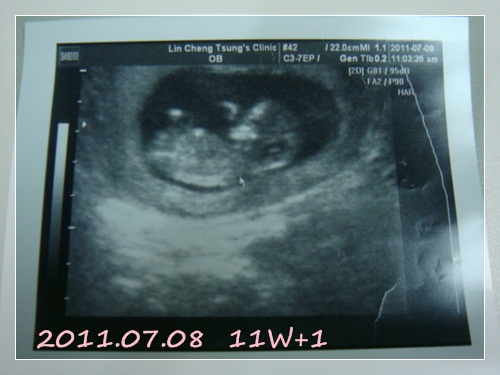

11W+1 (第二次產檢) 二寶:5.26cm初期的產檢都是每月一次

熬呀熬,終於可以再去看看二寶